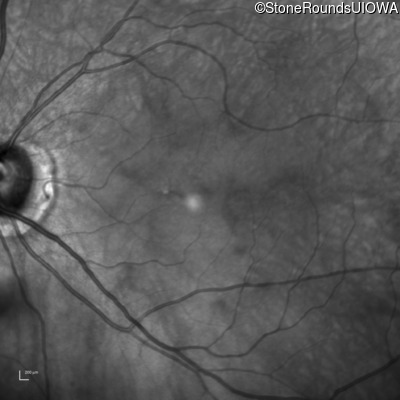

Infrared Fundus Photograph - Right - 20/300

Exemplar

Infrared Fundus Photograph - Left - 20/150